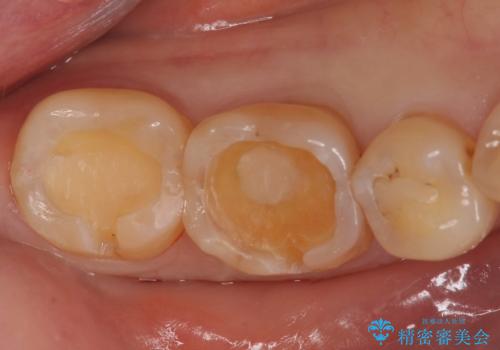

奥歯がしみる。

- 奥歯がしみるとのことで来院。レントゲンを確認したところ虫歯はなかったが、歯の咬む面がすり減っていました。

歯ぎしりがとても強い方で、セラミックの詰め物だと割れてしまう可能性があることを伝えたところ、なるべく割れにくいものが良いとのことでしたので、ゴールドインレーによる治療を行いました。